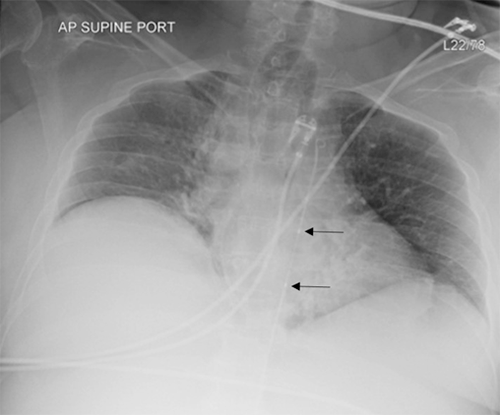

A 60-year-old female presented in hypertensive crisis, with systolic blood pressure over 200mmHg, to an outside facility. While in the hospital, she developed severe pain, abdominal distension, and hypotension. Computerized tomography (CT) scan revealed intra-abdominal hemorrhage within the lesser sac near the head of the pancreas. She was transfused and underwent angiography by interventional radiology. No clear bleeding source was seen, but there was a blush in the lesser sac, and thus the gastroduodenal artery was coil embolized. Her hemodynamics remained labile, and she was transferred to our facility. At the outside facility, the patient received eight units of packed red blood cells (PRBC), seven units of fresh frozen plasma (FFP), and six platelets. The patient received an additional PRBC, FFP, and platelet in transport. She arrived in extremis, being actively transfused and receiving vasopressors. She received an additional five PRBCs, one FFP, and a Zone 1 REBOA was placed and inflated to 10mL (Figure 1). Systemic heparin was not given due to ongoing hemorrhage.

Figure 1. Chest Radiograph Indicating Zone 1 REBOA Placement. Published With Permission

Radiopaque marker bands (arrows) denote proximal and distal margin of balloon.